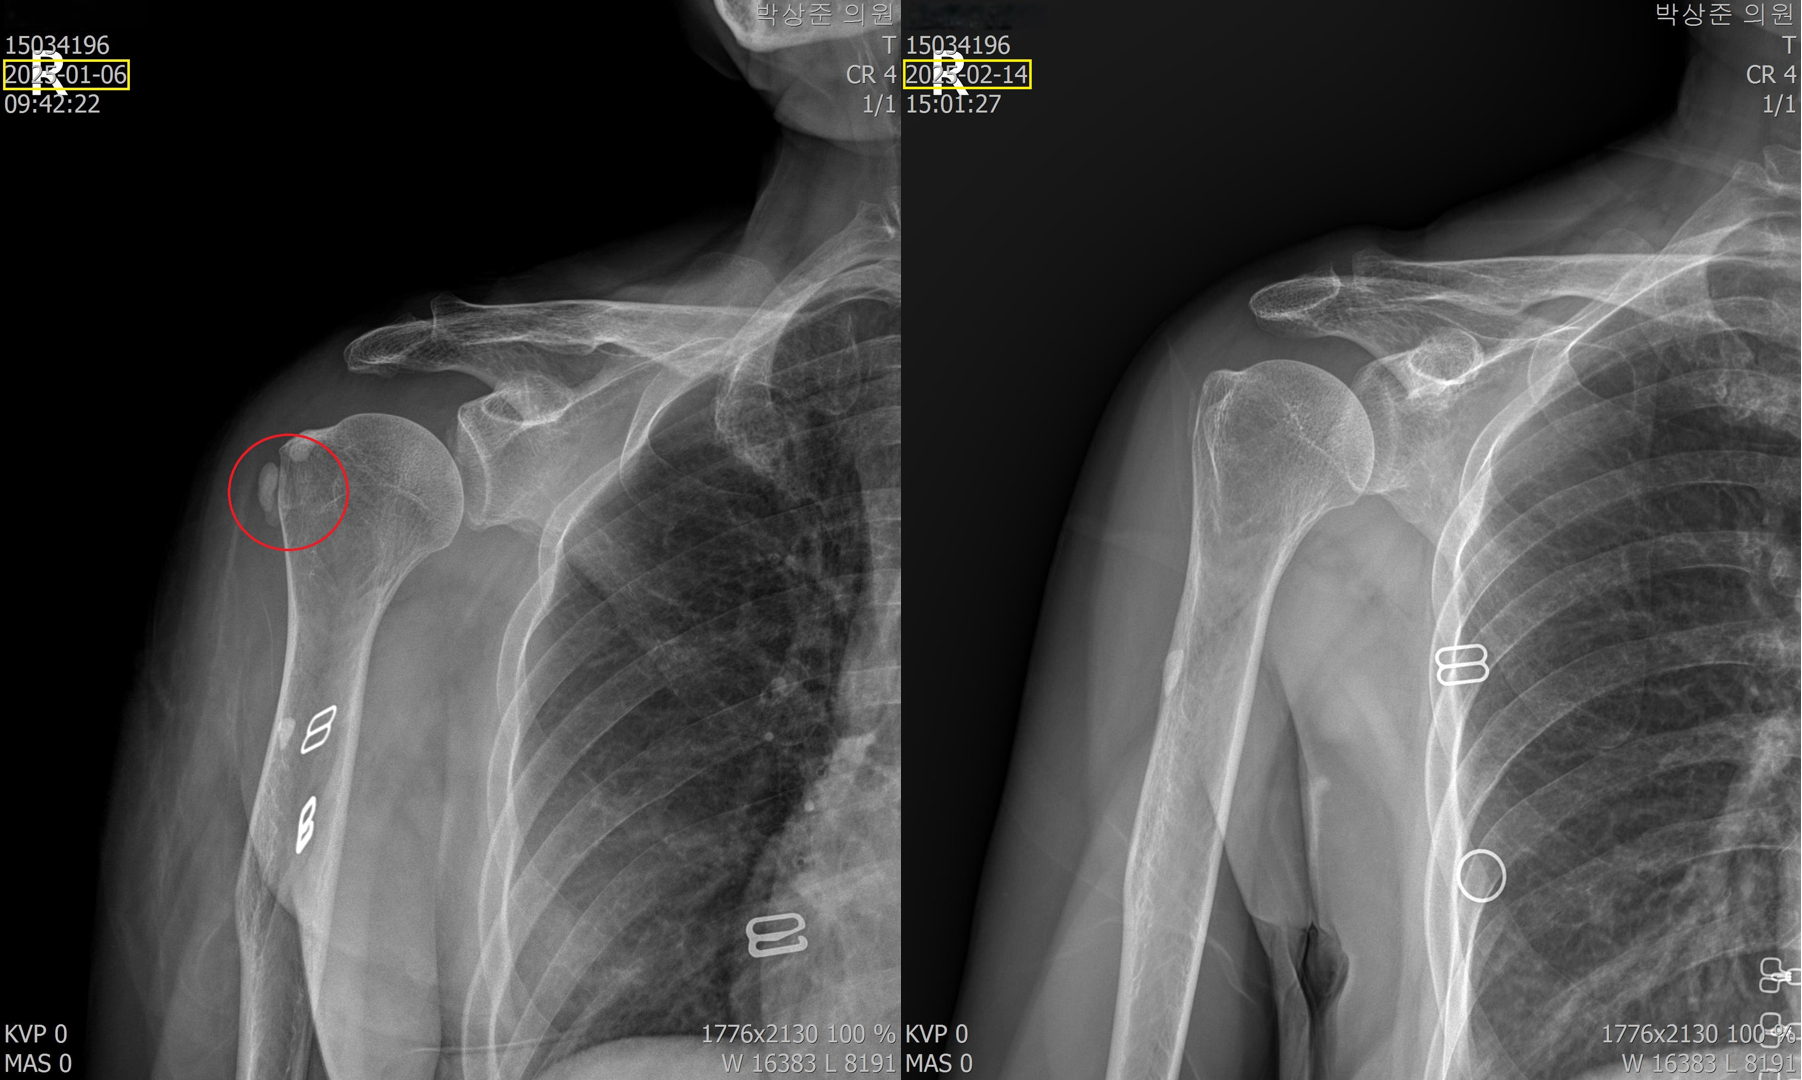

위의 비포 & 애프터 사진을 보면 알 수 있지만 5회의 석회 흡입술과 체외충격파 치료로 아주 커다란 석회가 드라마틱하게 사라진걸 볼 수 있습니다. 이 환자분의 경우 염증 주사를 맞고 이틀만에 통증은 거의다 사라졌고 커다란 석회마저 완전히 제거되어 치료 만족도가 매우 높은 분이었습니다.